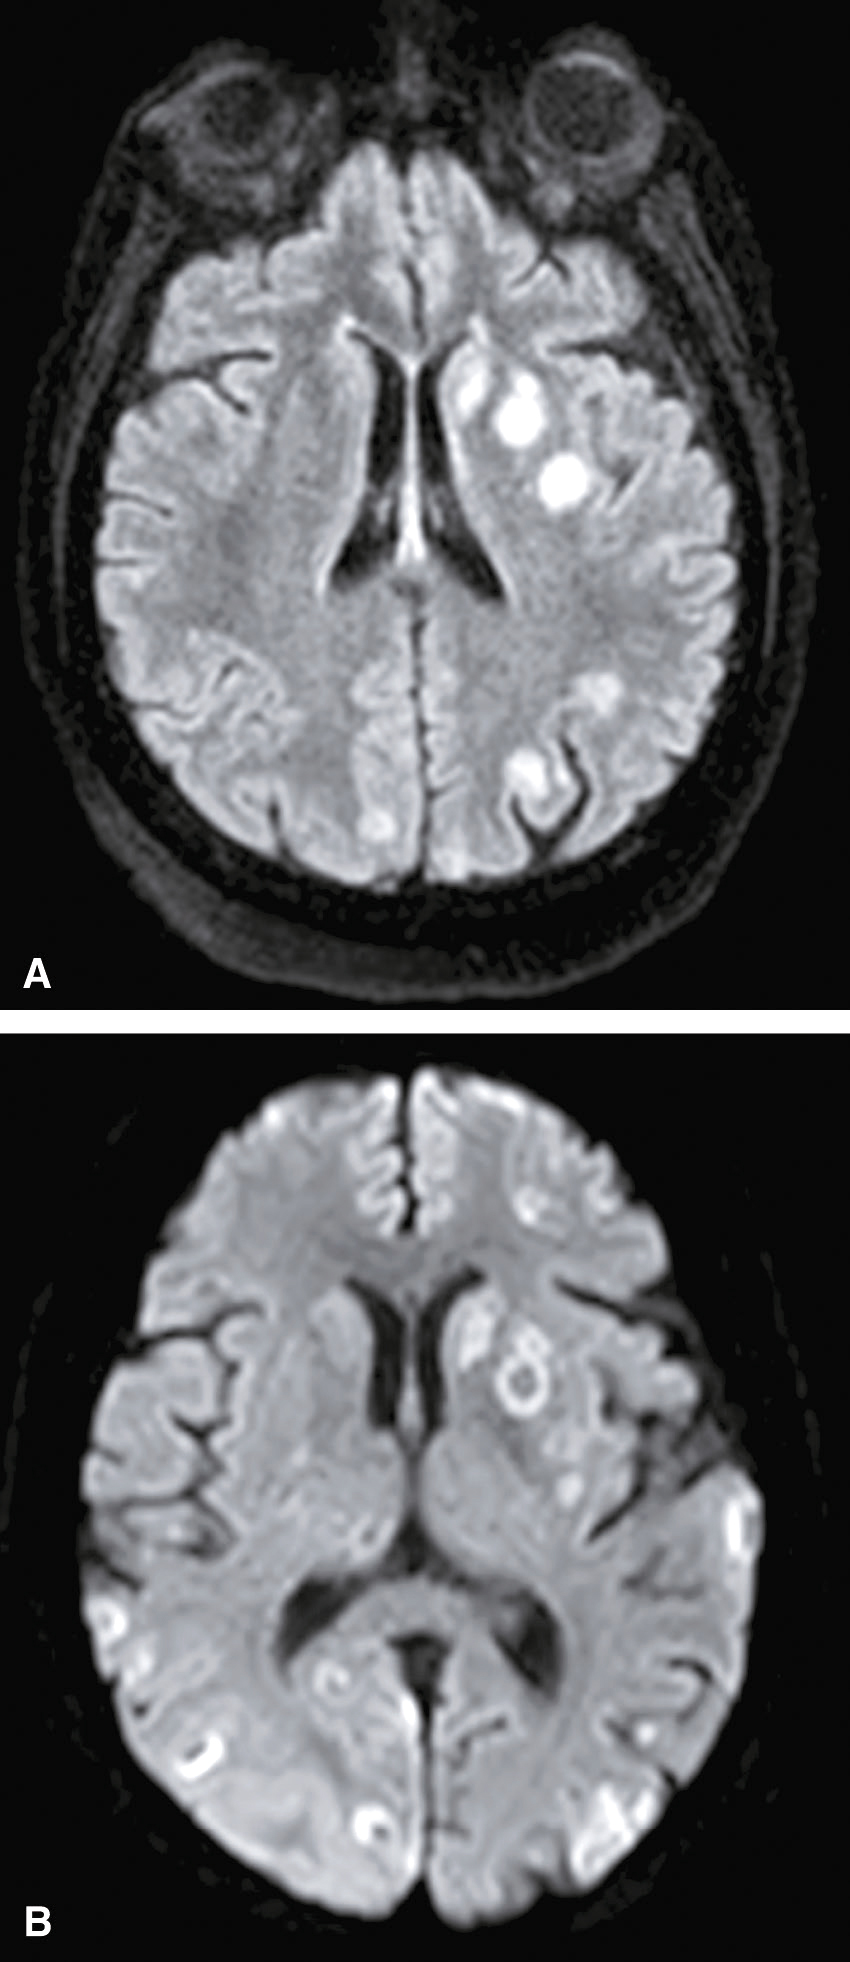

Une IRM encéphalique est réalisée (fig. 31.7). Sur cette planche, quels sont les éléments évocateurs du diagnostic de sclérose en plaques (SEP) ?

L'image montre trois coupes transversales d'un cerveau humain prises par imagerie par résonance magnétique (IRM). Chaque coupe est étiquetée avec des informations spécifiques : "FH 14 head", "FH 20 head" et "FH 26 head". Ces étiquettes indiquent probablement différentes sections ou niveaux de la tête. Les images montrent des zones de signal hyperintense, qui apparaissent comme des taches blanches sur les images. Ces zones peuvent indiquer des anomalies telles que des lésions, des plaques ou d'autres types de pathologies cérébrales. Les coupes transversales permettent de visualiser différentes parties du cerveau, y compris les ventricules cérébraux et la matière blanche environnante. Les images sont intéressantes car elles permettent de détecter et de surveiller des conditions neurologiques, d'évaluer l'étendue des dommages et de planifier des traitements appropriés. Les variations dans les images peuvent fournir des informations cruciales sur la progression de la maladie ou l'efficacité des interventions thérapeutiques.

- A 585présence d’hypersignaux de la substance blanche

- B localisation surtout périventriculaire des hypersignaux

- C aspect arrondi des hypersignaux

- D présence de trous noirs

- E atrophie cérébrale marquée